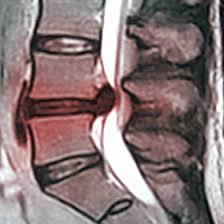

Siamo in grado di guarire dall’ernia discale lombare senza bisogno del bisturi, con semplici esercizi fisici da eseguire a domicilio?

Che l’ernia del disco lombare non sia obbligatoriamente chirurgica è ormai assodato: la maggior parte dei Pazienti nemmeno pensa all’intervento, se non quando il danno sul nervo è veramente insopportabile. E fin qui ci siamo. Naturalmente, è necessario discriminare da caso a caso.

Ma in generale, spesso le ernie passano MENTRE facciamo qualcosa, piuttosto che GRAZIE A quel qualcosa che proviamo a fare. Quindi l’ernia discale lombare è una patologia che guarisce spontaneamente, come l’influenza.

Possiamo provare a facilitare questa guarigione, dal momento che il tempo è il parametro fondamentale, perché se l’ernia guarisce, ma prima di guarire ha avuto tempo di schiacciare il nervo e danneggiarlo in modo irreversibile beh, allora forse è meglio correre a farsi operare. Buona parte delle ernie discali sono contenute al disotto del legamento “longitudinale posteriore”, che come un elastico tende a spingerle nuovamente dentro il disco.